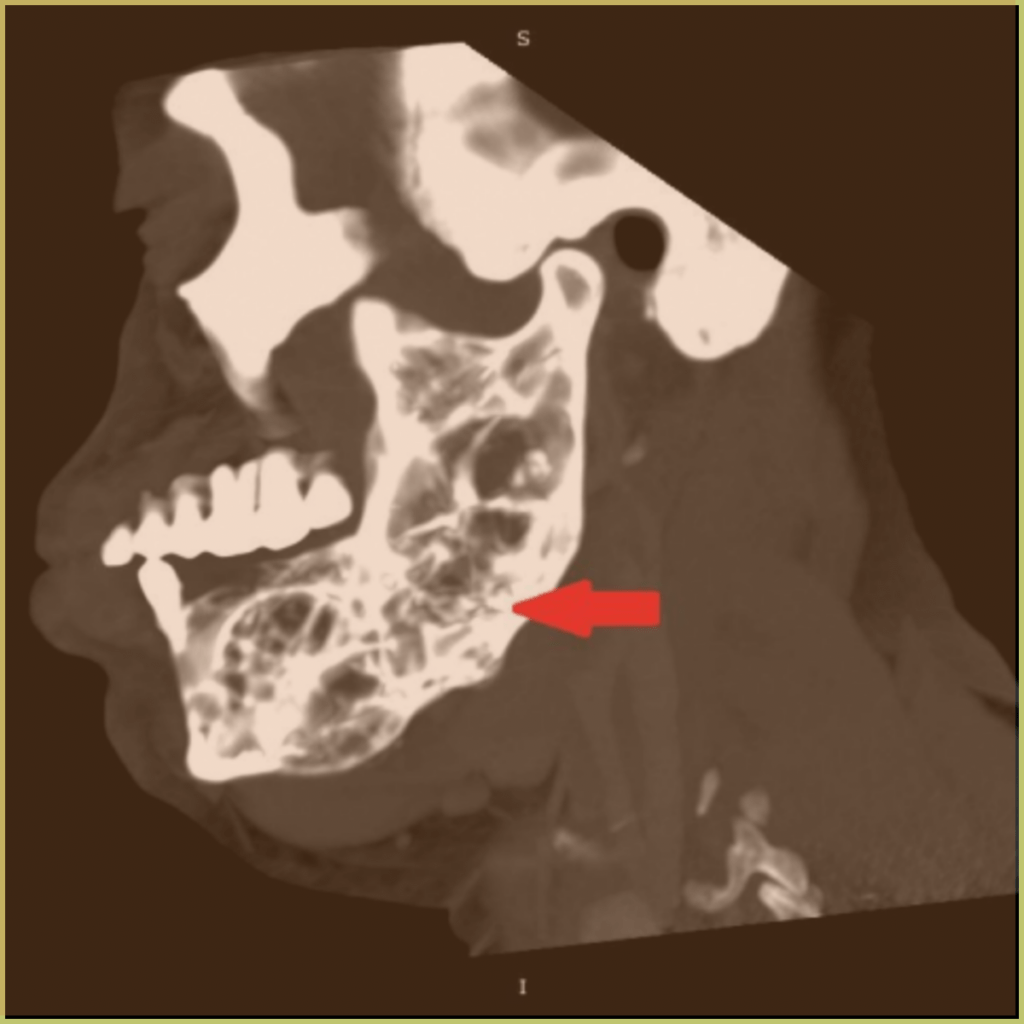

ODONTOMAS

Odontomas are the most common hamartomatous benign mixed odontogenic tumors of the jaw, composed of all the building blocks of teeth (enamel, dentin, cementum, and pulp tissue). They develop from stimulation of the epithelial dental lamina. Variants include compound odontomas (small tooth-like structures), complex odontomas (aggregation of dentin, enamel and cementum) and cystic odontomas. The common clinical presentation includes:

- Well-defined mixed radiolucent and radiopaque lesions.

- Visible within the alveolar segment of the maxilla and mandible.

- Complex form is the most common in the mandible, compound form is the most common in the anterior maxilla.

- May contain a few small “teeth” or large numbers of tiny tooth-like structures.

- Asymptomatic and usually discovered incidentally.

- Can cause alveolar expansion, jaw expansion, and interfere with tooth eruption.

Diagnosis is based on the lesion history, clinical presentation and microscopic findings, which usually includes evidence of dental hard tissues. Your differential diagnosis should include:

Treatment usually involves conservative excision or curettage only.